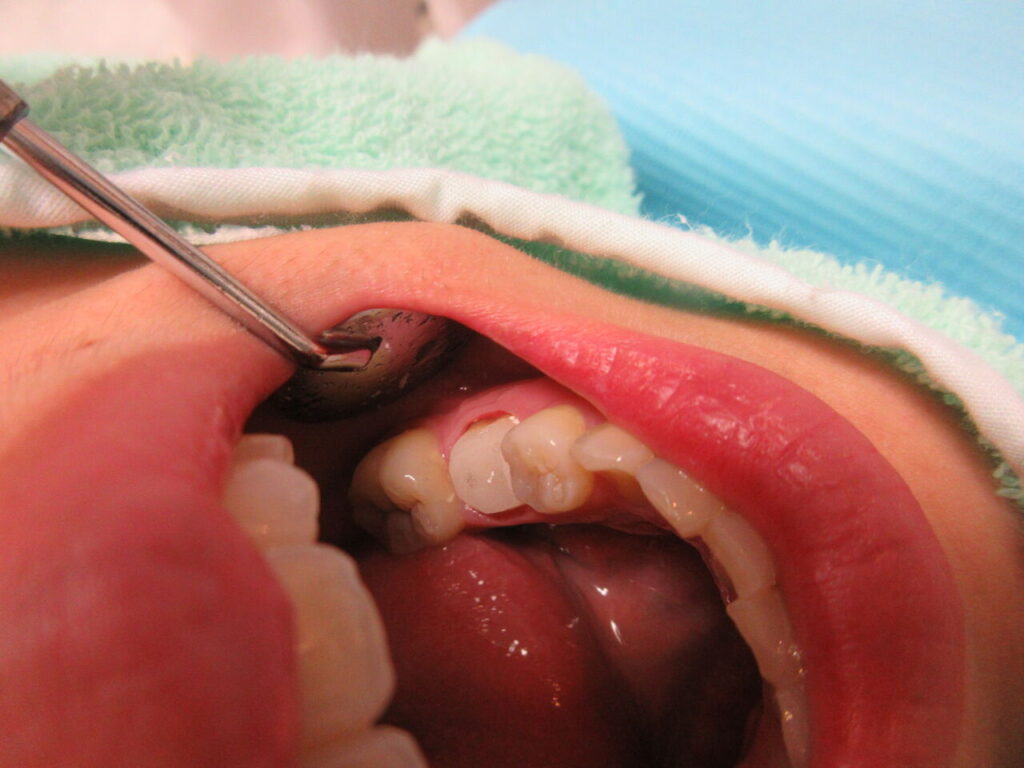

一番多い製作物はファイバーコアとジルコニアのセットです。